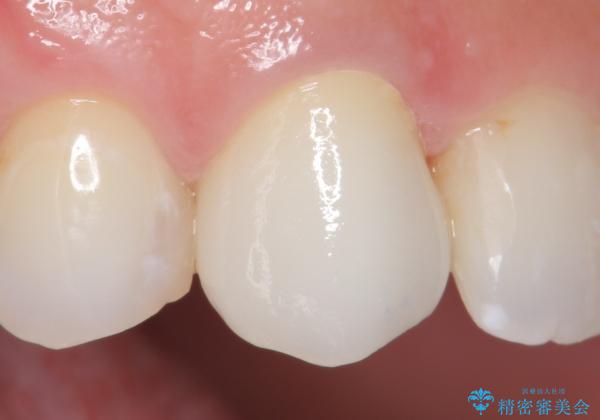

前歯の補綴ではオールセラミッククラウンを希望される患者様が多いですが、オールセラミッククラウンの中でも、エコノミー、スタンダード、スペシャル、エクセレントとランクがあります。

その中でも特に審美性が高いのがスペシャル、エクセレントです。スペシャル、エクセレントは口腔内写真をもとに熟練の技工士が、患者様の口腔内に合わせたオーダーメイドのクラウンを製作致します。